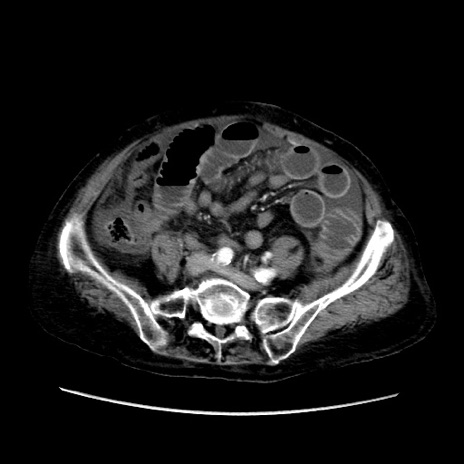

矢状断像